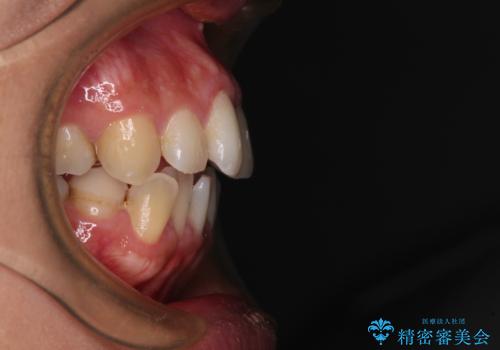

前歯のデコボコを改善 インビザラインの矯正治療

- 前歯のデコボコを治したいとのことで来院された患者様です。

上下顎ともに歯列全体の後方移動とIPR(歯と歯の間を削る)によってデコボコが解消するように設計し、インビザラインにより治療を行うこととしました。